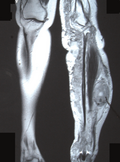

| current | 20:14, 10 June 2009 |  | 1,096 × 1,480 (2.4 MB) | Filip em | {{Information |Description={{en|1=MRI image showing the site of the tumor in the left tibia}} |Source=Malignant peripheral nerve sheath tumor in neurobifromatosis type-1: two case reports [http://casesjournal.com/casesjournal/article/view/7612/3538 PDF] | |